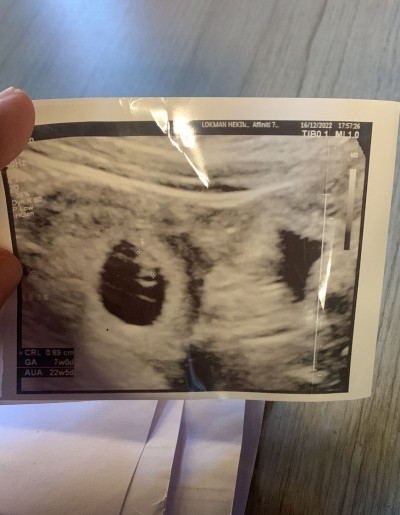

Kızlar merhaba, fotoğraf arkadaşıma ait.Kendisi 8 haftalık hamile.2 hafta kadar önce yerleşme kanaması oldu ve beta hcg değeri hep olması gerekenden çok yüksek.Kendiside ikiz olduğu için biz ikiz gebelik olabilir diye düşünmüştük.Ama bugün bir doktor,görünen ikinci kesenin yolk kesesi olduğunu, tek gebelik olduğunu söylemiş.Biz doktora güvenemedik malesef.Bu durumu yaşayan varmı?Sizce ikiz gebelik mi?

Bir kesede bebek var canım digeri boş sanki

Aynı şeyi yaşadım 2 kese vardı,  biri. Boş kendiliğinden kayboldu

Bende de bu şekildeydi ama tek gebelik mevcut şuan diğer kese boş duruyor